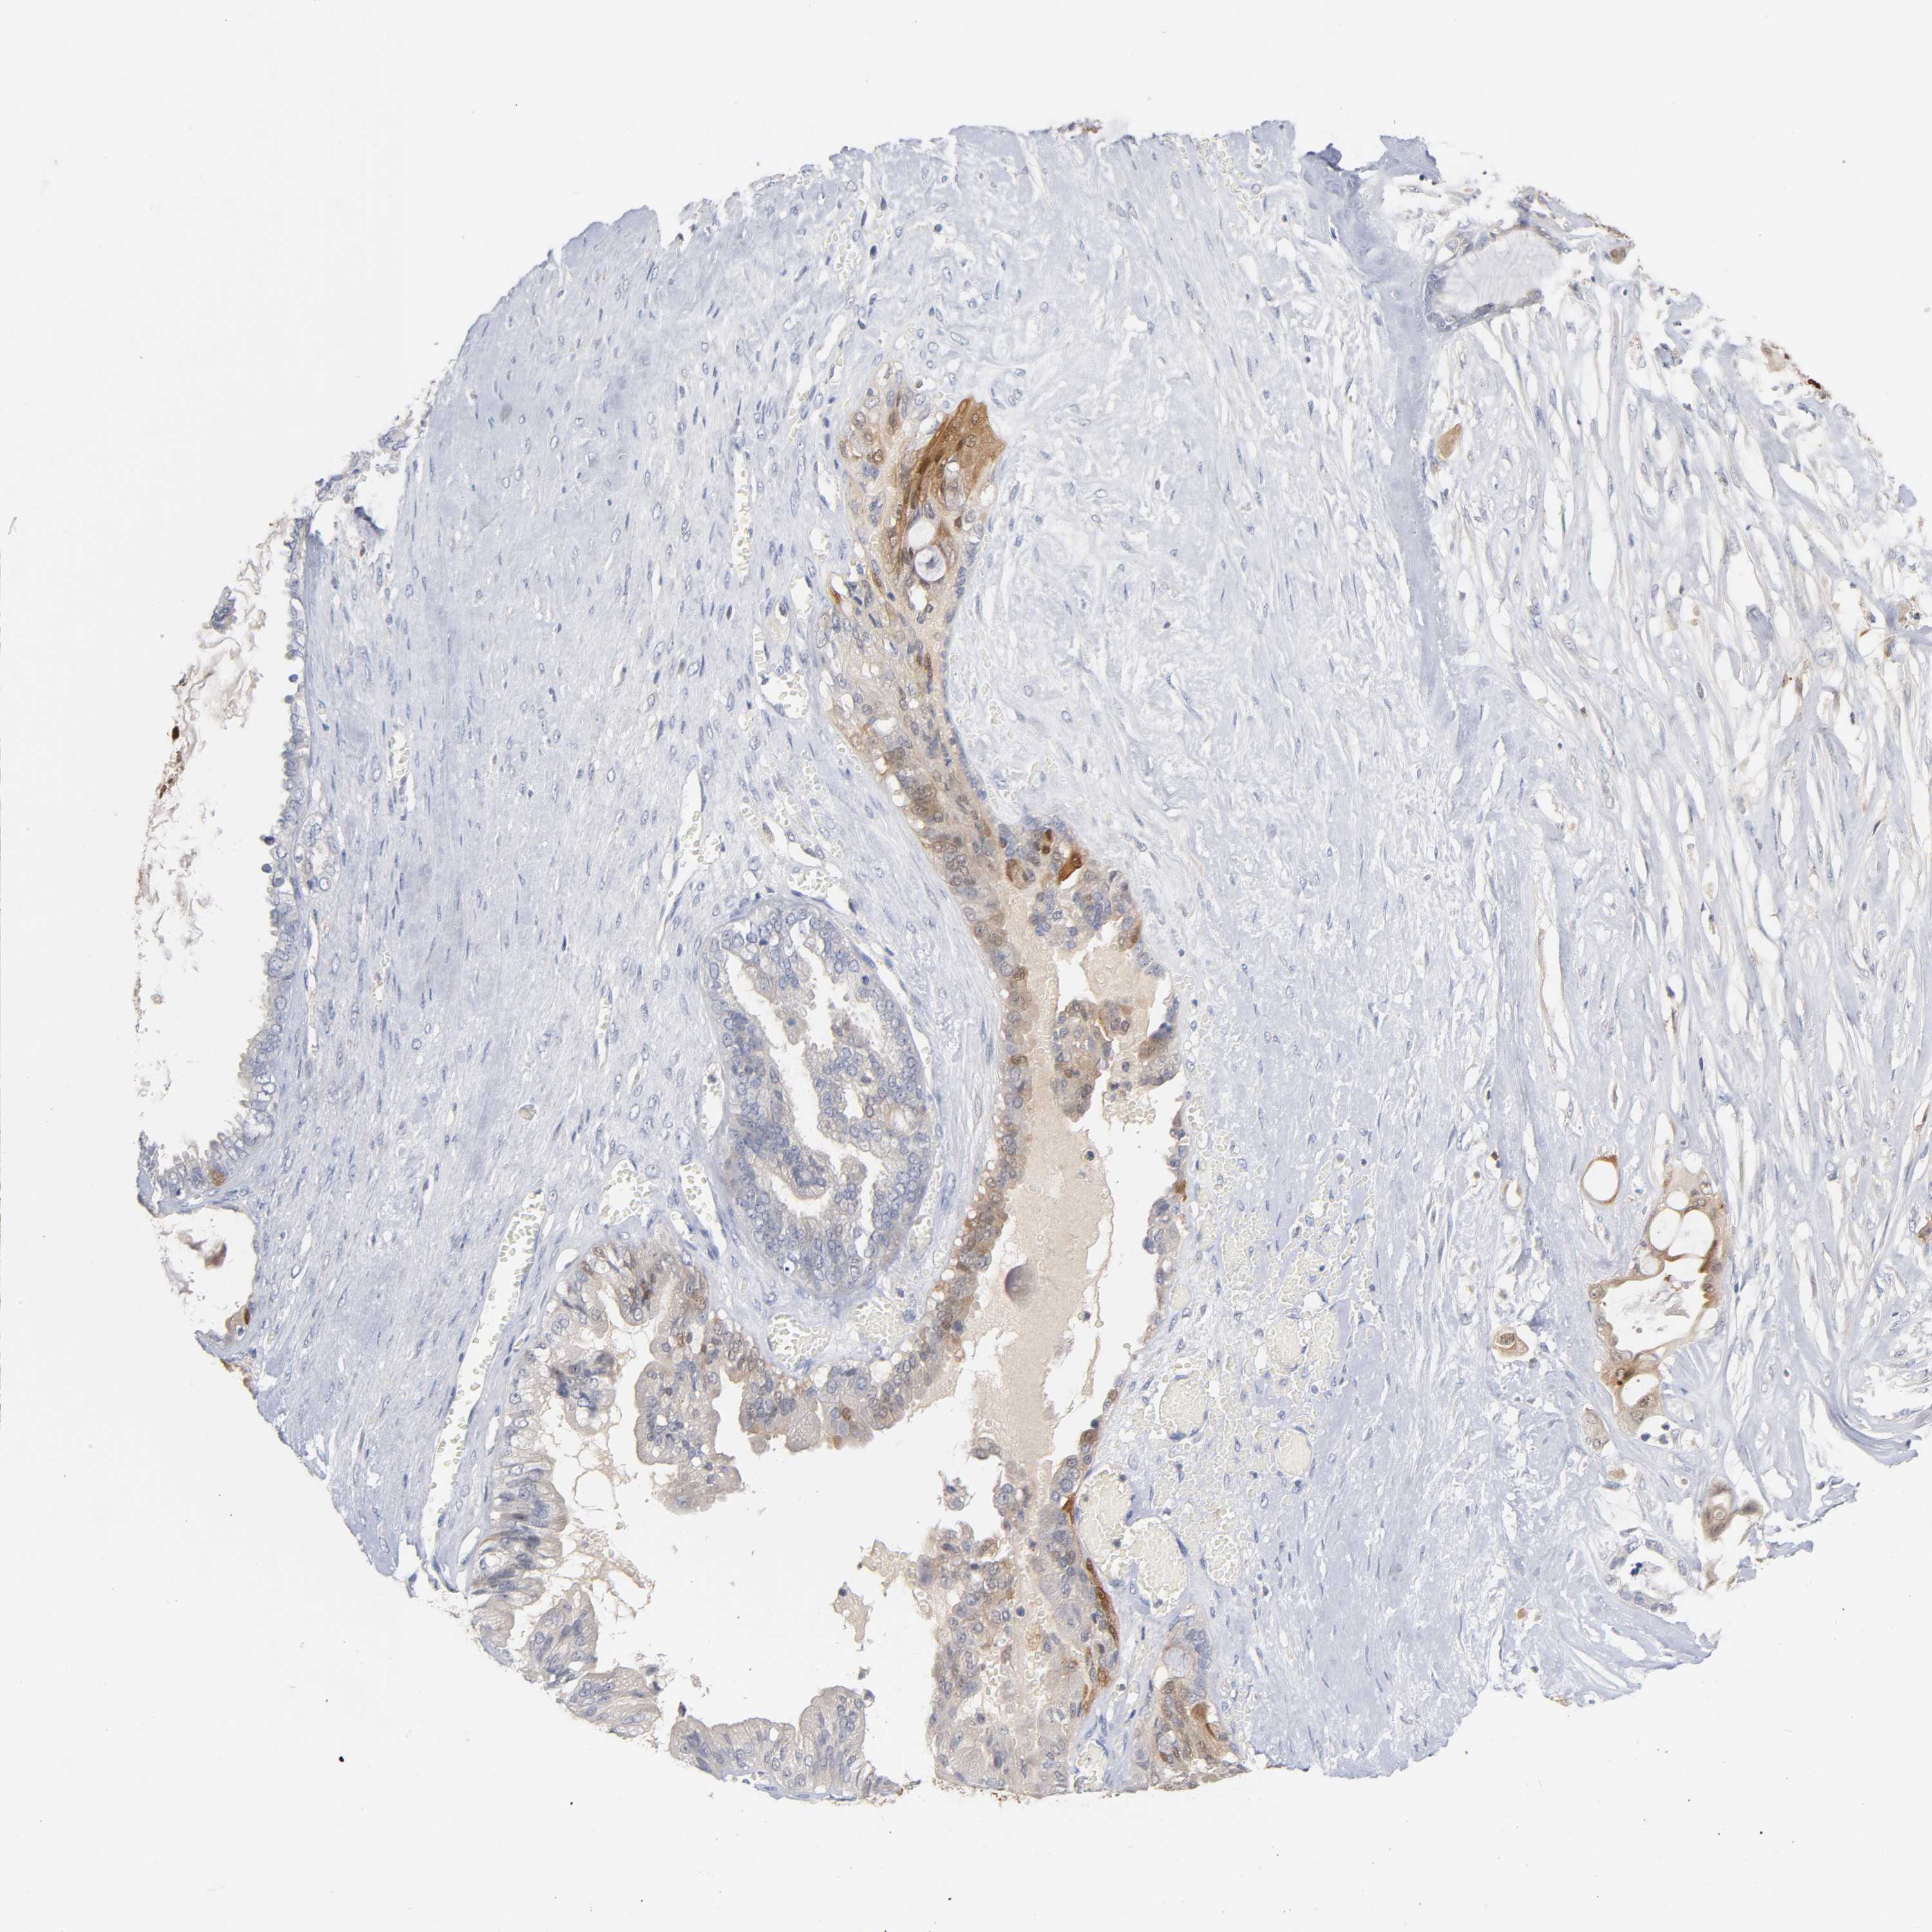

OVARIAN CANCER - Protein expressioni

A mouse-over function shows sample information and annotation data. Click on an image to view it in a full screen mode. Samples can be filtered based on level of antibody staining by selecting one or several of the following categories: high, medium, low and not detected. The assay and annotation is described here.

Note that samples used for immunohistochemistry by the Human Protein Atlas do not correspond to samples in the TCGA dataset.

Antibody stainingi

Antibody staining in the annotated cell types in the current human tissue is reported as not detected, low, medium, or high, based on conventional immunohistochemistry profiling in selected tissues. This score is based on the combination of the staining intensity and fraction of stained cells.

Each image is clickable and will lead to virtual microscopy that enables deeper exploration of all samples and also displays staining intensity scores, fraction scores and subcellular localization as well as patient and tissue information for each sample.

Antibody HPA003980

Antibody CAB007772

Staining

High

Medium

Low

Not detected

Intensity

Strong

Moderate

Weak

Negative

Quantity

>75%

75%-25%

<25%

None

Location

Nuclear

Cytoplasmic/membranous

Cytoplasmic/membranous,nuclear

Carcinoma, endometroid

Carcinoma, NOS

Cystadenocarcinoma, serous, NOS

Cystadenocarcinoma, mucinous, NOS